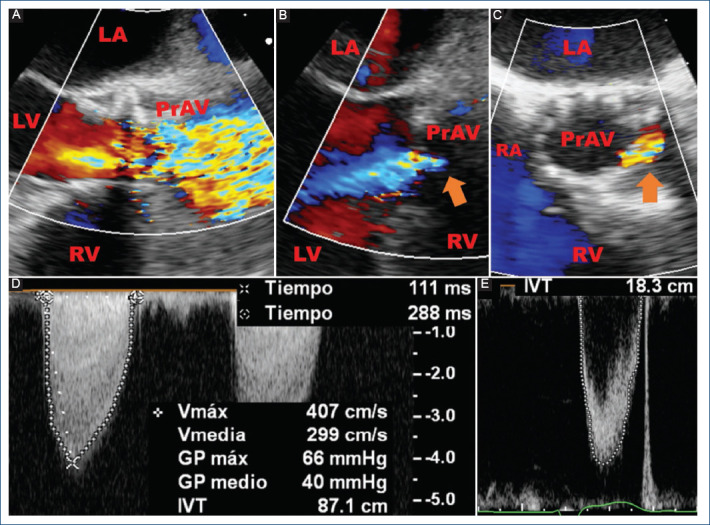

Staphylococcus lugdunensis endocarditis causing prosthetic aortic valve dysfunction after TAVR.